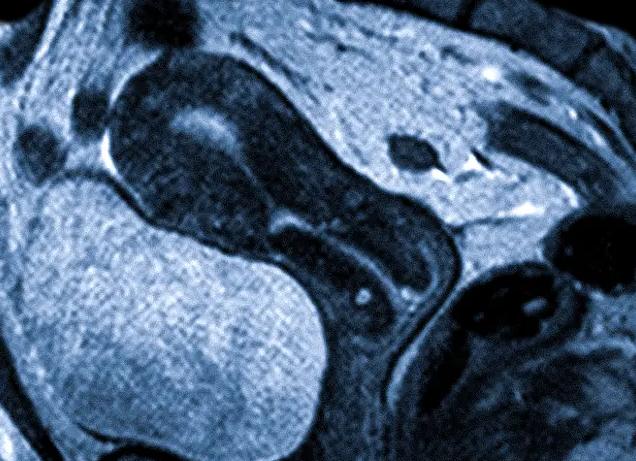

Магнитный резонанс – достаточно часто назначаемое обследование, которое отличают безопасность и высокий уровень точности. Исследование проводится на специальном аппарате, получившем название томограф. Принцип его работы заключается в получении электромагнитных импульсов от датчиков, которые крепятся к телу человека. Собранные данные затем поступают в компьютер, где анализируются. В результате на экран выводится трехмерный снимок органа.